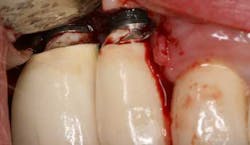

Fig. 4: Probing around implant-supported crown reveals depth and suppuration.

Fig. 5: Surgical intervention revealed retained cement.